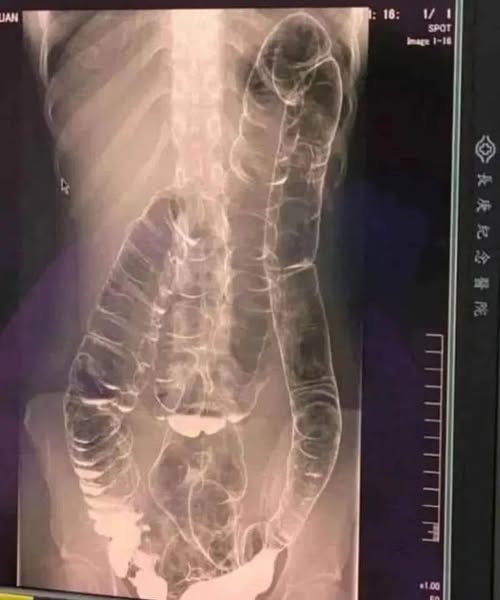

Ez egy krónikus székrekedésben szenvedő fiatal nő röntgenfelvétele. Miután több mint két héten át tartós tüneteket tapasztalt, orvoshoz fordult, és megkapta az alábbi röntgenfelvételek eredményét…

A székrekedés szinte mindenkit utolér időnként. Gyakran egy apró kellemetlenségnek tűnik, ám ha rendszeressé válik, komoly gondokat hozhat. Volt olyan fiatal nő, akinek olyan mértékben feltorlódtak a salakanyagok, hogy a vastagbele veszélyesen kitágult. Hogyan előzhetjük meg, hogy ez az emésztési panasz súlyosabbra forduljon?